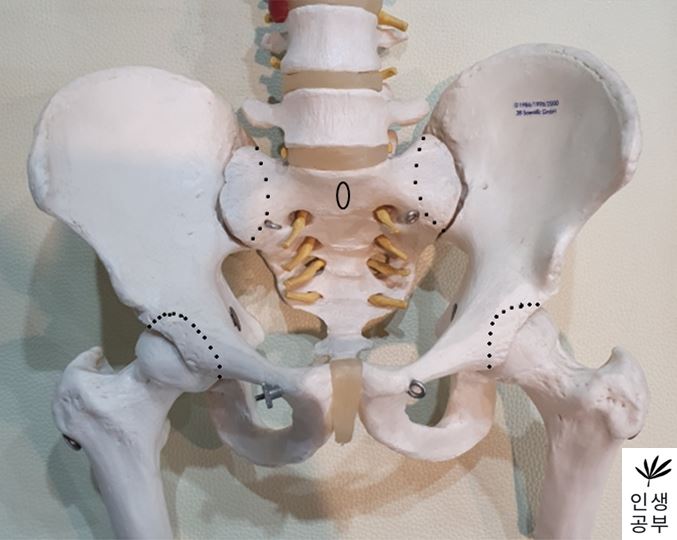

X-RAY에서 골반이 EX/IN를 어떻게 알 수 있는지에 대해서 알아보겠습니다. EX는 한쪽 골반(EX 측 골반)이 엉치뼈(Sacrum)가 있는 방향의 반대 방향으로 (배꼽 쪽으로) 가는 것을 말하고 반대로 IN은 엉치뼈(Sacrum)가 있는 방향으로 한쪽 골반(IN 측 골반)이 향하는 것을 가리킵니다. 그럼 어떻게 알 수 있는지에 대해서 선 그리는 방법을 통해서 알아보겠습니다.

1. 골반 X-ray 선 그리는 방법(EX/IN)

1) X-ray를 준비합니다.

2) 대퇴골두(Femoral head) 최상단에 양쪽에 각각 한개씩 점을 찍어줍니다.

3) 두 점을 연결하는 선을 긋습니다. 이 선의 이름은 대퇴골두선(FHL : Femur Head Line)이라고 합니다.

4) 1번째나 2번째 엉치뼈 결절(sacral tubercle) 정가운데 점을 찍어줍니다.

5) 치골결합(pubic symphysis) 정가운데에도 점을 찍어줍니다.

6) 1번째나 2번째 엉치뼈 결절(sacral tubercle) 정가운데 찍은 점에서 대퇴골두선(FHL : Femur Head Line)을 기준으로 수직인 선을 긋습니다.

선을 그었을 때 점이 있는 쪽 골반이 IN이 됐다는 뜻이고, 없는 쪽은 EX 되었다는 뜻입니다.